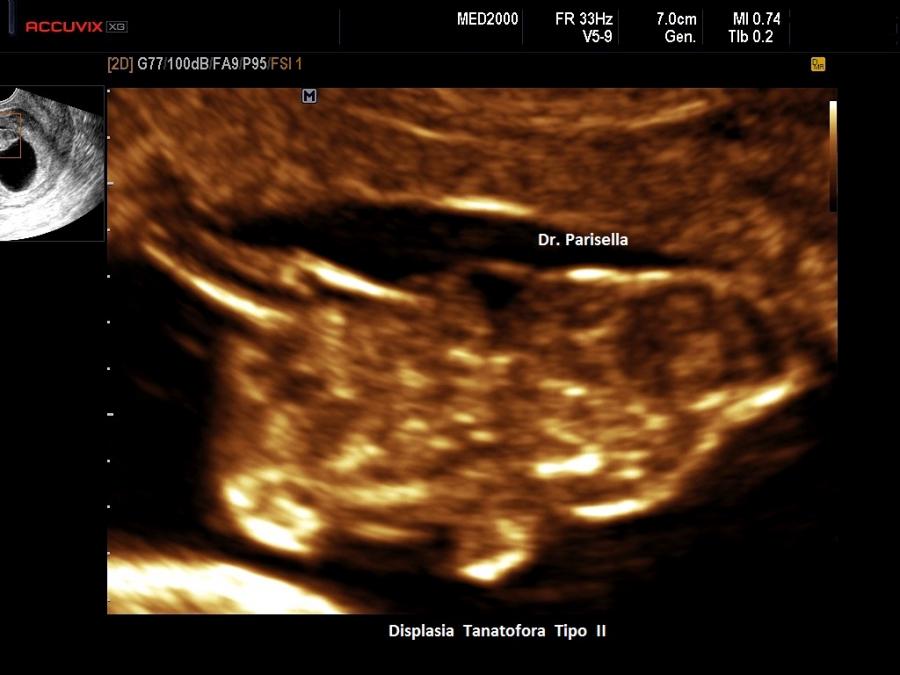

La Displasia Tanatofora tipo II è trasmessa con modalità autosomica dominante ed è caratterizzata da MICROMELIA SEVERA, IPOPLASIA TORACICA SEVERA e CRANIO A TRIFOGLIO.

Dal punto di vista ecografico la presenza contemporanea di MICROMELIA e CRANIO A TRIFOGLIO rappresentano una associazione di notevole rilevanza diagnostica per questa patologia.

Il cranio a trifoglio è evidenziabile in scansione coronale ed è dovuto alla sinostosi delle suture lambdoidea, coronale e sagittale e conseguente prominenza delle regioni temporali. Caratteristicamente in questi casi si ha molta difficoltà a misurare il Diametro Biparietale.

Le ossa lunghe appaiono meno ipoplasiche e ricurve che nel Tipo I.